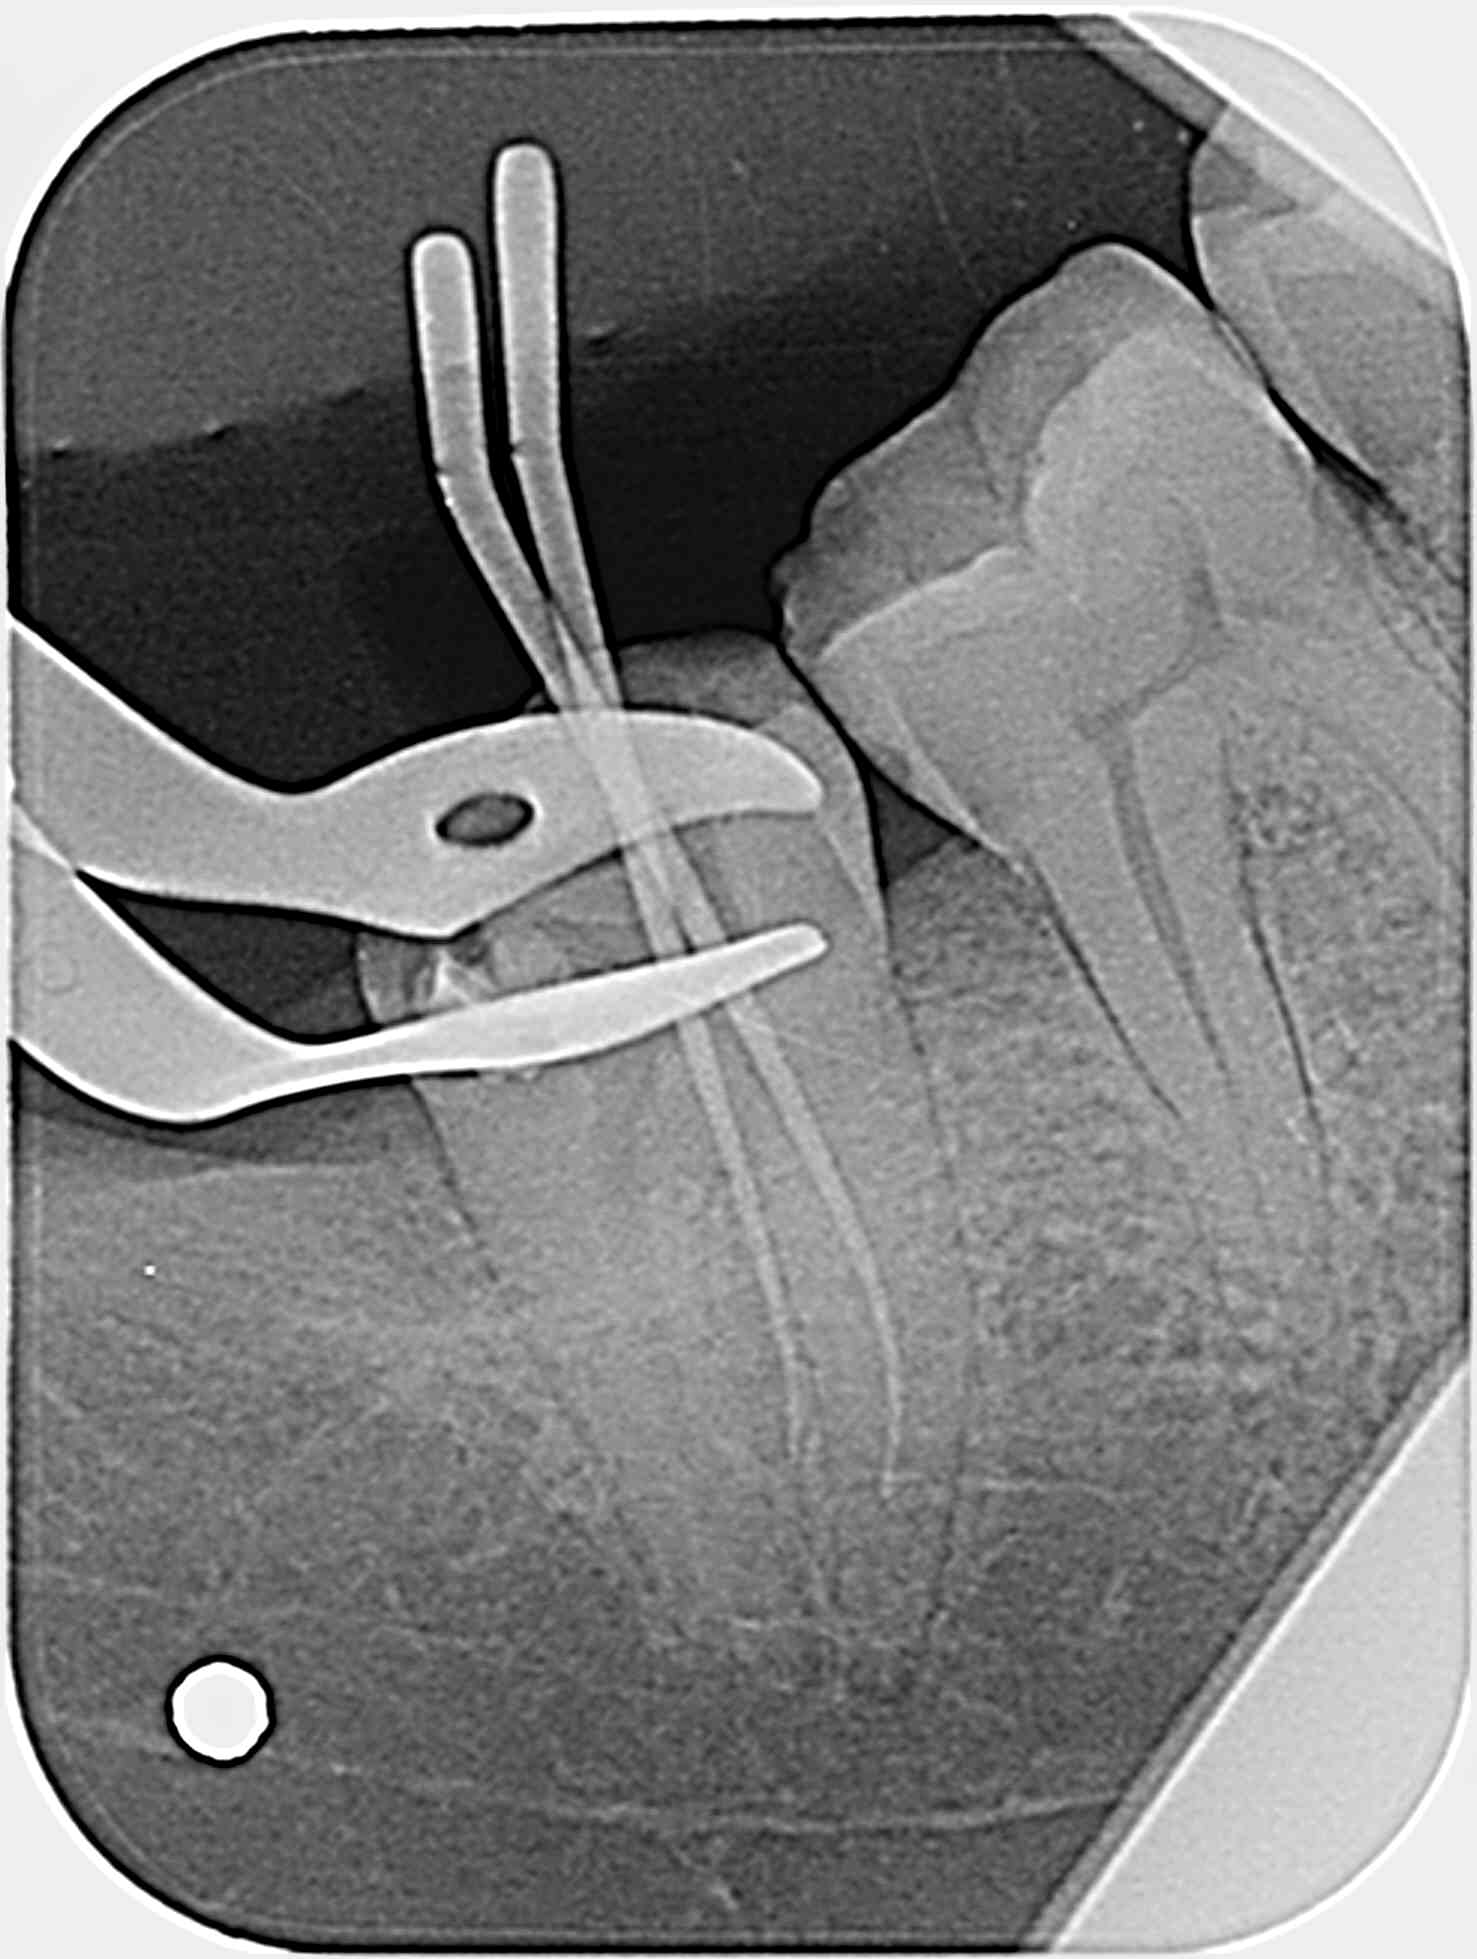

Je fais une radio per-op avec deux cônes de gutta fins de diamètre 20 4% dans les deux canaux mésiaux et … surprise…

Qu'en pensez-vous ?

1/Mon ML correspond a un canal secondaire qui va du plancher pulpaire vers l'espace interdentaire ? Ou bien ML dans racine que je ne vois pas (je ferai des radios excentré prochaine fois)?

Tes cônes sont sensés être dans les deux mésiaux ? Si oui ce pseudo canal secondaire n'est pas le DV...

Je suis assez sur que ce n'ai pas une perf, donc si localisateur sonne tôt, canal secondaire partant de la chambre vers espace inter radiculaire ? Dans ce cas la je n'ai que deux canaux, un MV et un Distal excentré en vestibulaire.

Bon après lecture des réponses et réflexion, j'opte (j'espère); soit, le moins probable, pour un canal secondaire de la chambre vers l'espace inter radiculaire, soit, le plus probable pour une anatomie en C donnant l'impression que mon MV est en inter radiculaire (type TIB postée par BURNAX).